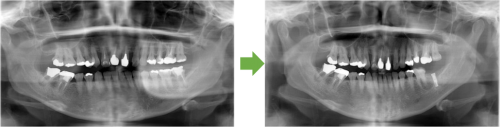

インプラント 左下の奥歯 川口で精密インプラント治療なら さかえ歯科クリニック